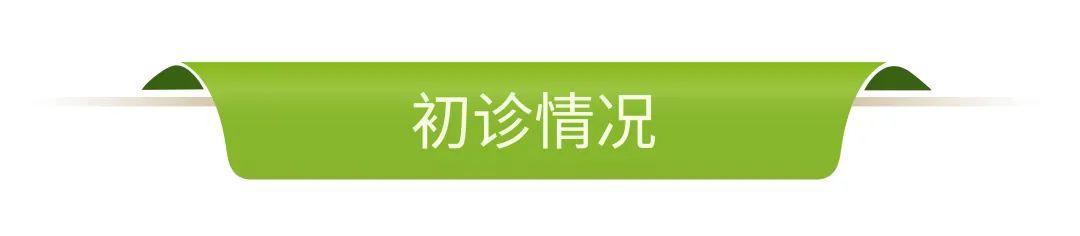

影像学检查

· 缺牙区骨量尚可,余留牙骨吸收至根尖1/3 。

· 双侧髁突骨皮质连续。

· 头影测量分析,临床诊断为:上颌前突,骨性二类错合畸形,上下中切牙及上下唇前突。

· 根据患者诉求、面型、剩余骨量、余留牙状况,拟拔除全部余留牙行全口种植固定修复。

· 上下颌计划各植入六颗straumann钛锆种植体行即刻种植即刻修复。